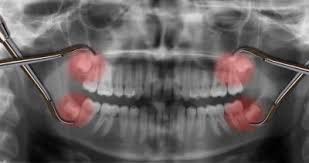

Teilweise durchgebrochene Weisheitszähne sind die wahrscheinlichsten Ausrichtungen die entfernt werden müssen. Vorab lässt sich sagen dass es in keinem Fall empfehlenswert ist den Durchbruch der Weisheitszähne oder die mit ihm verbundenen Probleme zu ignorieren. Die Fäden zieht der Zahnarzt in der Regel nach 7-10 Tagen.

Wie schon beschrieben kann es dazu kommen dass sie erheblichen Druck auf den restlichen Zahnbestand ausüben und zu Fehlstellungen oder Verschiebungen von diesem führen. Dann versperren andere Zähne den Weg oder der Zahn wächst schief.